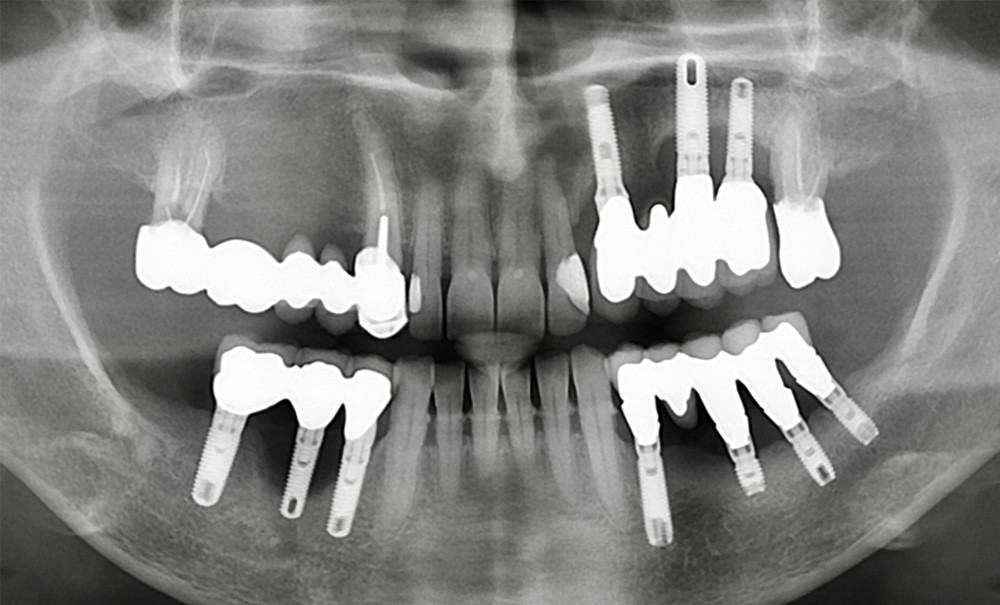

La plupart des implants utilisés jusqu’au début des années 2000 présentaient des surfaces usinées, donc relativement lisses. On parlait peu de péri-implantite à cette époque. Ces surfaces ont été remplacées par des surfaces modérément rugueuses, dites surfaces modifiées. Des voix se sont élevées pour mettre en cause ces nouvelles surfaces et leur attribuer une part de responsabilité dans la prévalence aujourd’hui élevée de la péri-implantite (un patient sur cinq). Mais les avis divergent sur ce sujet, comme l’illustrent les deux articles suivants.

Leur réponse s’appuie sur une revue systématique récente de la littérature [1] qui conclut : « Les expériences précliniques in vivo indiquent que les caractéristiques de surface des implants modifiés peuvent avoir un impact négatif significatif sur la progression de la péri-implantite, tandis que les études cliniques ne soutiennent pas l’idée qu’il existe une différence dans l’incidence de la péri-implantite entre les différents types de surfaces d’implant. »

En termes simples, dans les études animales, la progression de la péri-implantite est plus rapide si la surface de l’implant est rugueuse. Chez l’homme, à l’inverse, une surface rugueuse n’est pas un facteur de risque.

Fin de la polémique. Nous pouvons continuer à utiliser des implants à surface rugueuse tels que fabriqués par la plupart des sociétés. Ces surfaces modifiées, introduites en 2000 pour remplacer les surfaces usinées plus lisses, ne sont pas responsables de la prévalence élevée (1 patient sur 5) et bien documentée de la péri-implantite [3-11].